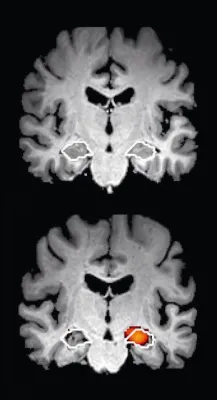

(openPR) Die Diagnostik der Alzheimererkrankung ist eine aufwändige Prozedur, da viele Alzheimer-typische Symptome auch anderen Erkrankungen zugeordnet werden können. Das Ausschlussverfahren hierzu ist für Ärzte aufwändig und für Patienten mühselig und belastend. Eine neue Studie belegt eindrucksvoll, dass die automatisierte Hippokampusvolumetrie eine signifikante Aussagekraft bei der Diagnose der Erkrankung hat.

Obwohl bereits als Diagnosemerkmal in den europäischen Leitlinien enthalten, konnte die Hippokampusvolumetrie bisher nur in wenigen, meistens akademischen Zentren durchgeführt werden. Wichtige Voraussetzung zur Anwendung des Verfahrens war das tiefgehende Anwendungswissen, technologische Kompetenz und die Erfahrung des befundenden Arztes. Seit der Einrichtung von Referenzzentren vor zwei Jahren wurde das Verfahren der automatischen Hippokampusvolumetrie kontinuierlich weiterentwickelt und überprüft. Das Ergebnis dieser Forschungsarbeit liegt nun vor. Ab sofort gibt es die Möglichkeit, mit frei verfügbaren Analysetools eine vollautomatische, computergestützte Hippokampusvolumetrie vorzunehmen. Deren Zuverlässigkeit wurde in einer Studie belegt und liegt bei einer Genauigkeit von 80%.

In der Studie wurde für 100 Gedächtnisambulanz-Patienten das Hippokampusvolumen mit dem frei verfügbaren Tool bestimmt und mit den Ergebnissen der klinischen Untersuchung verglichen.

Es zeigte sich, dass das Volumen des rechten Hippokampus ein zuverlässiger Parameter ist, Patienten mit einer Alzheimer-Erkrankung in einer Population von Menschen mit Gedächtnisstörungen zu identifizieren. Dabei belief sich die Dauer der vollautomatischen Berechnung des Hippokampusvolumens auf etwa vier Minuten. Damit kann mit einfachen Mitteln ein weiteres wichtiges Merkmal in den Diagnoseprozess eingebracht werden und die Sicherheit der Alzheimer-Diagnose erhöhen.